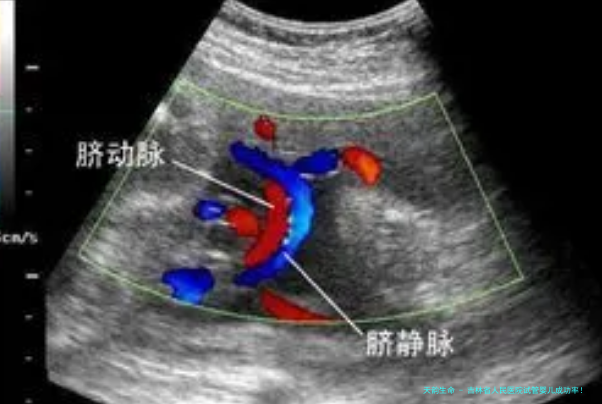

试管移植是1个邃密的环节,须要严格依照操作规范进行。移植过程当中,医生会将优良胚胎移植到女性子宫内,期望胚胎能够着床发生育。全部过程估计陆续五至十分钟,术后遗症者须要休憩察看,并准时复查监测怀孕情况。